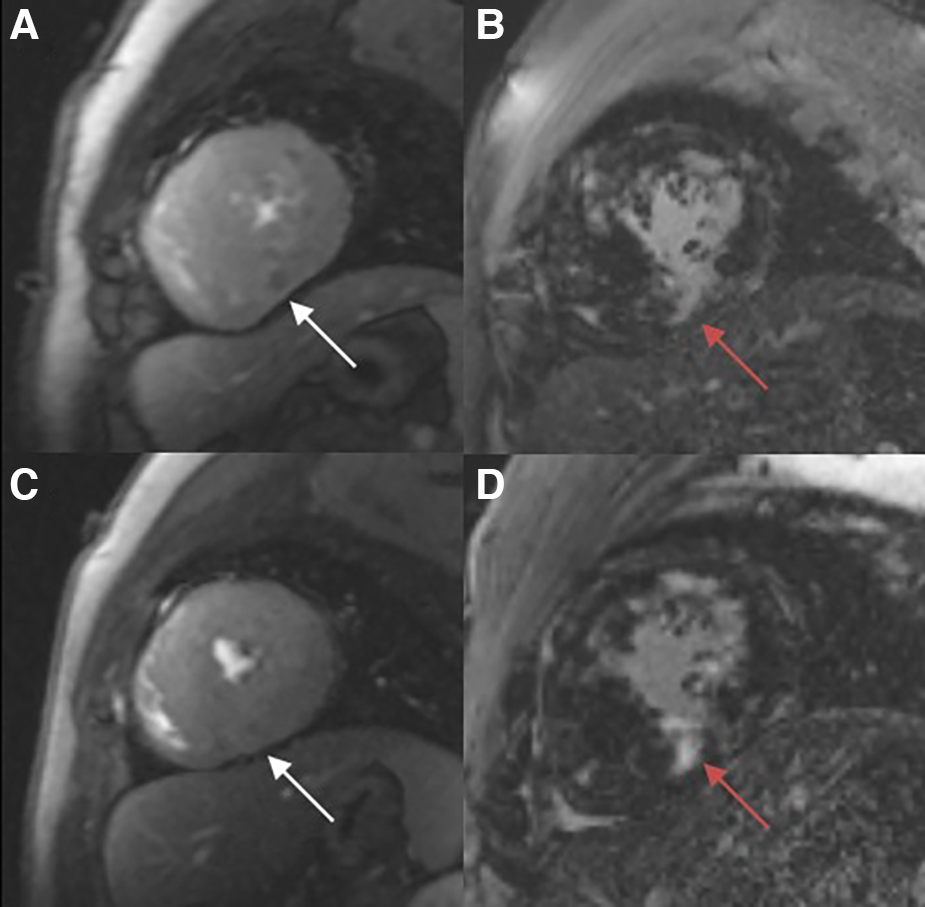

The Slopemax and Slmax were elevated, indicating that the blood filling rate and myocardial blood flow in the coronary microcirculation were significantly improved (Figures 3A,B). Similarly, the decrease in timemax means that the blood fully entered the cardiomyocytes more rapidly (Figure 3C). A representative case of myocardial perfusion before and after TA-BSM is shown in Figures 4, 5.

Figure 4

Myocardial perfusion examination (A, C) demonstrating a perfusion defect in the infer-septal midsegment on the images (white arrow). There are multiple patchy areas of late gadolinium enhancement (red arrow) in the myocardial segments with and without significant perfusion defects (B, D).